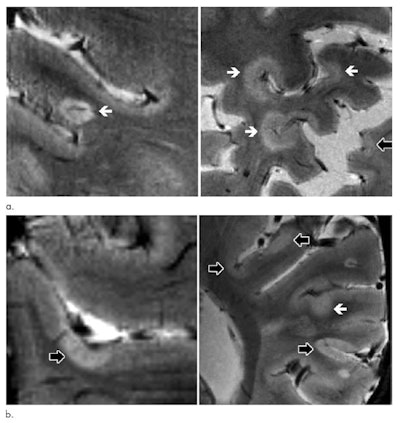

The new cortical lesions were also primarily located in the sulci rather than in the gyri, which is the ridge on the surface of the brain. New cortical lesions in the sulci would indicate a possible link with an ongoing cerebrospinal fluid (CSF) neuroinflammatory process. While the researchers do not have an explanation for the accumulation of lesions in the sulci, the flow of CSF is likely to be restricted in the area, making the sulci more vulnerable to inflammatory responses.

"These findings indicate that cortical lesions are likely driven by inflammatory events occurring in cerebral sulci, which previous neuropathologic examinations have reported as a preferential site of meningeal inflammation and possible restricted CSF flow with consequent stagnation of inflammatory soluble mediators," the authors wrote. "Our results also show that cortical lesion volume at baseline is related to EDSS progression independently from white-matter damage and cortical atrophy, highlighting the potential value of cortical lesion assessment at 7-tesla in the evaluation of progression of disease burden."